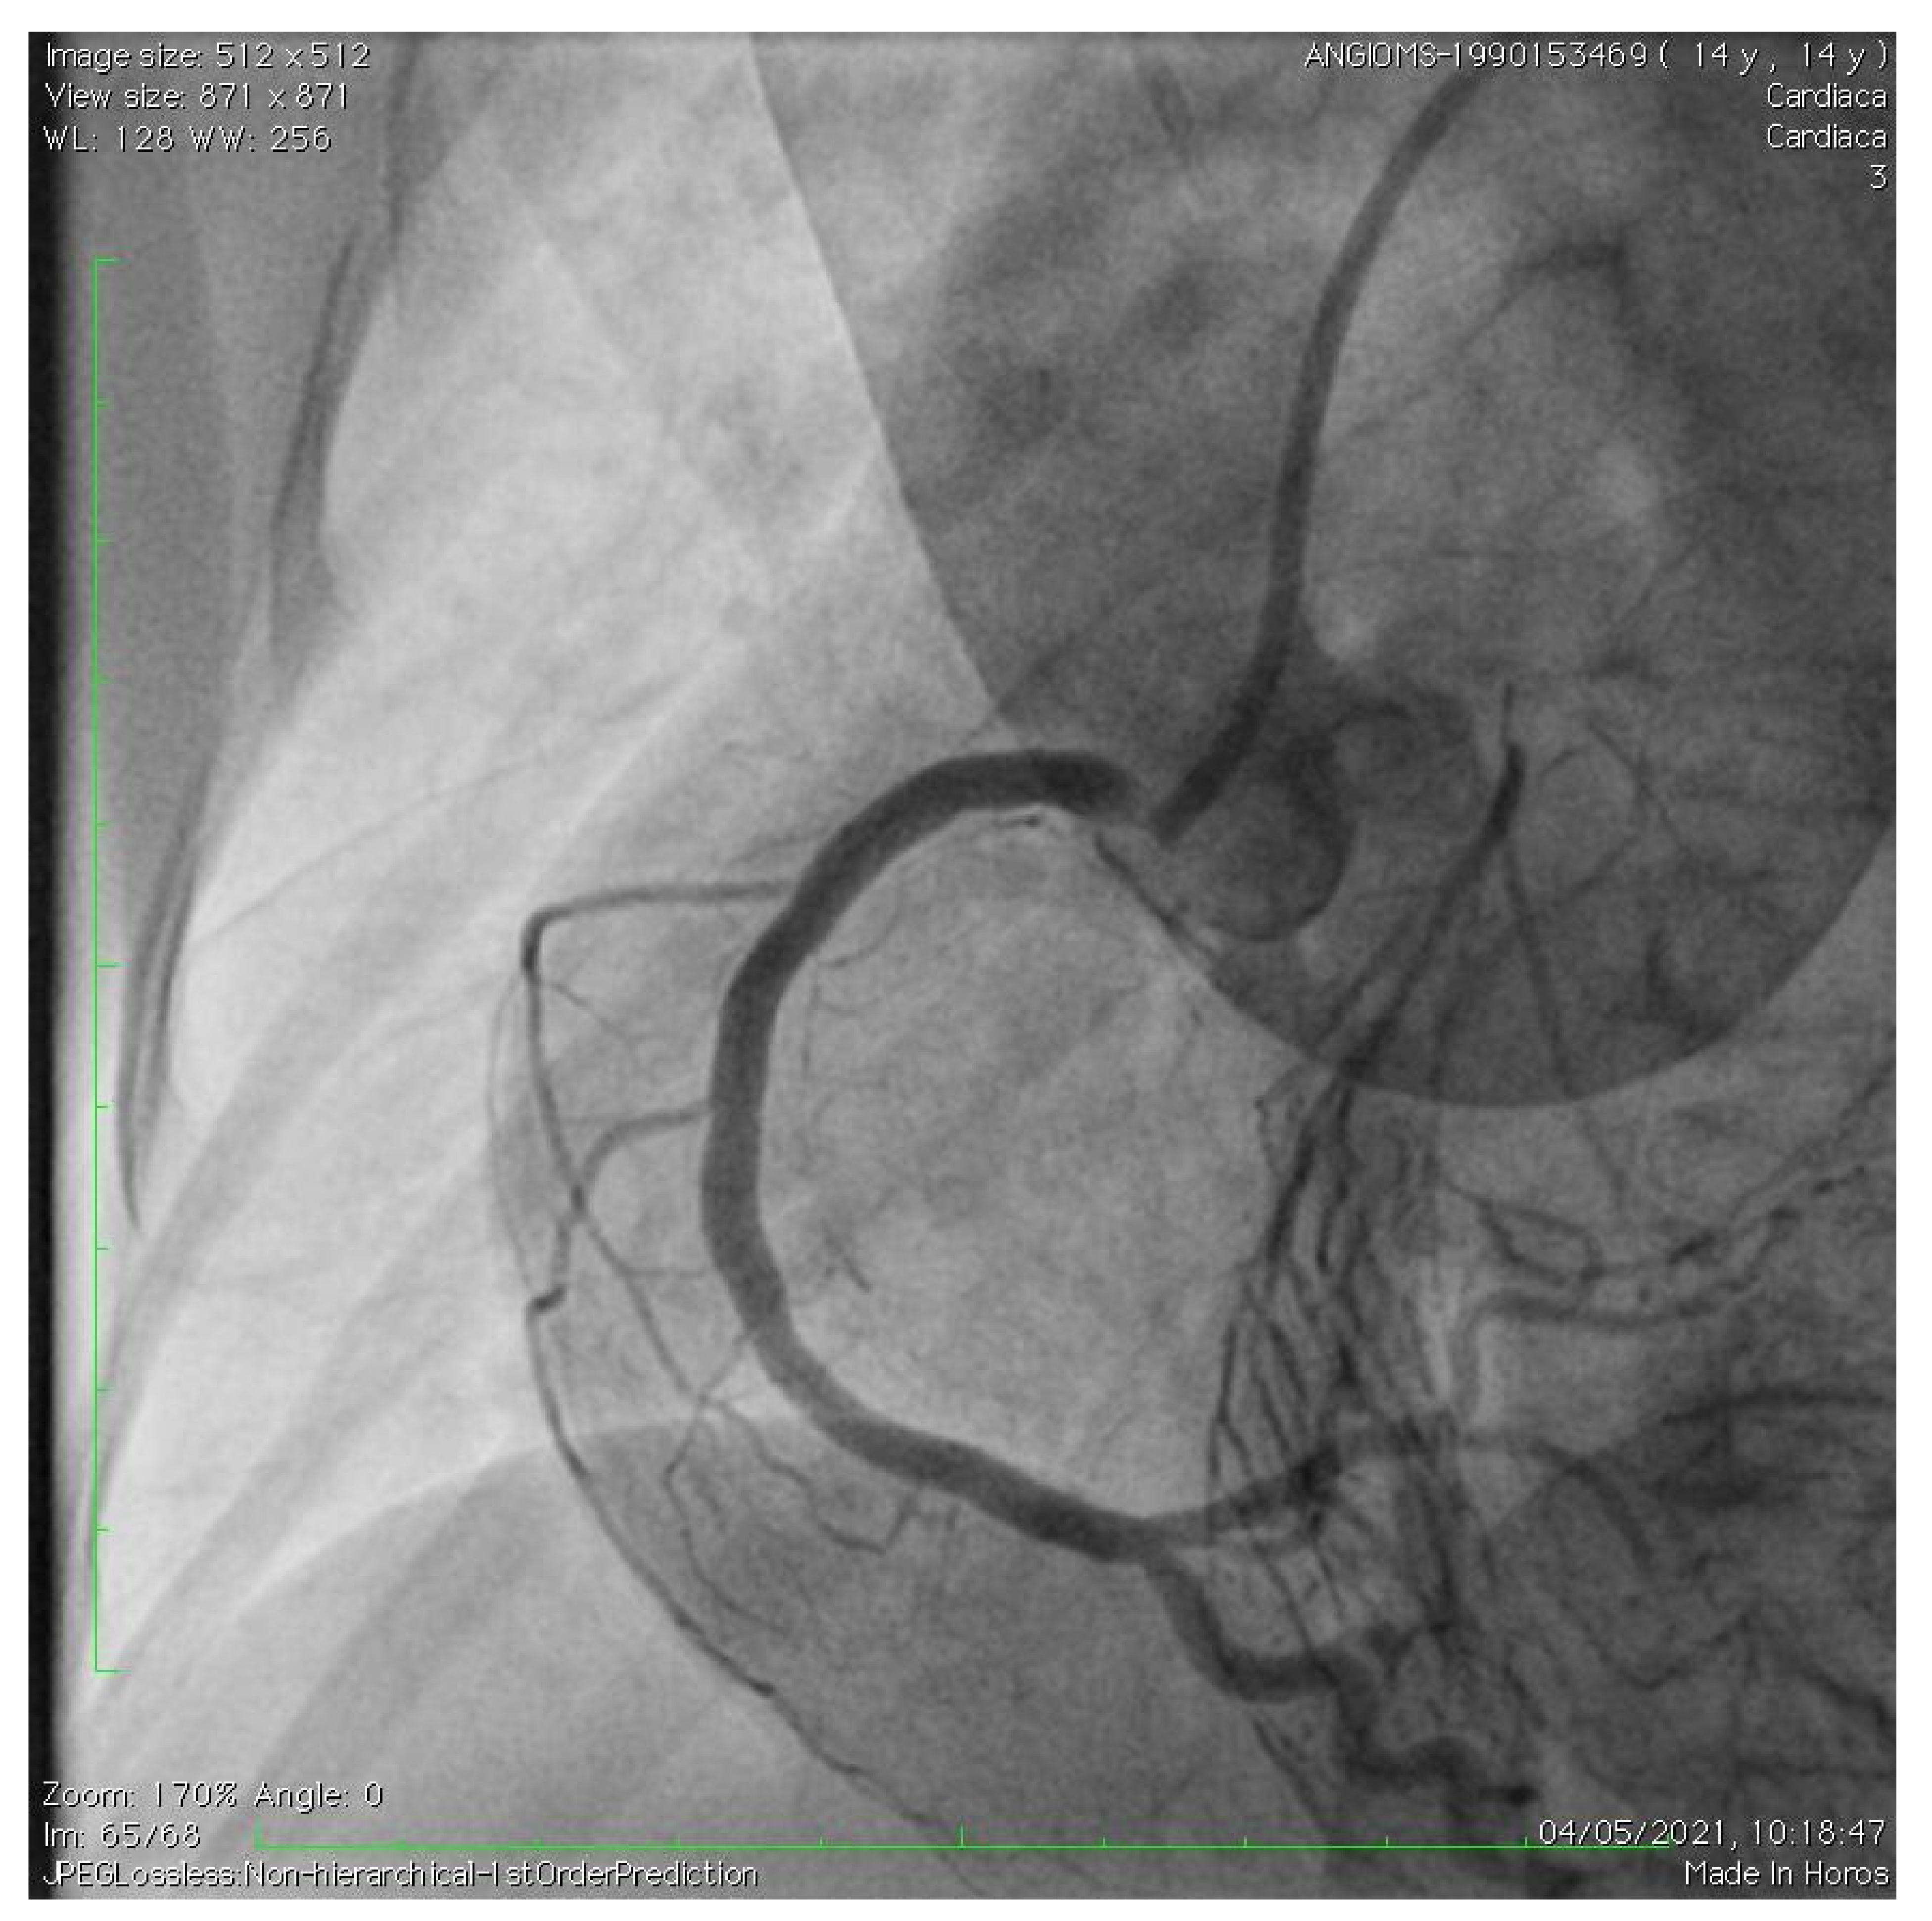

2. Case Description

- Roggen, M.; Dubois, C.; Gewillig, M. Coronary artery stenting in a patient with progeria. Catheter. Cardiovasc. Interv. 2017, 90, E38–E40. [Google Scholar] [CrossRef] [PubMed]

- Callahan, R.; Lock, J.E.; Shah, P.B.; Marshall, A.C. Transcatheter intervention of coronary ob structions in infants, children and young adults. Pediatr. Cardiol. 2018, 39, 1299–1307. [Google Scholar] [CrossRef]